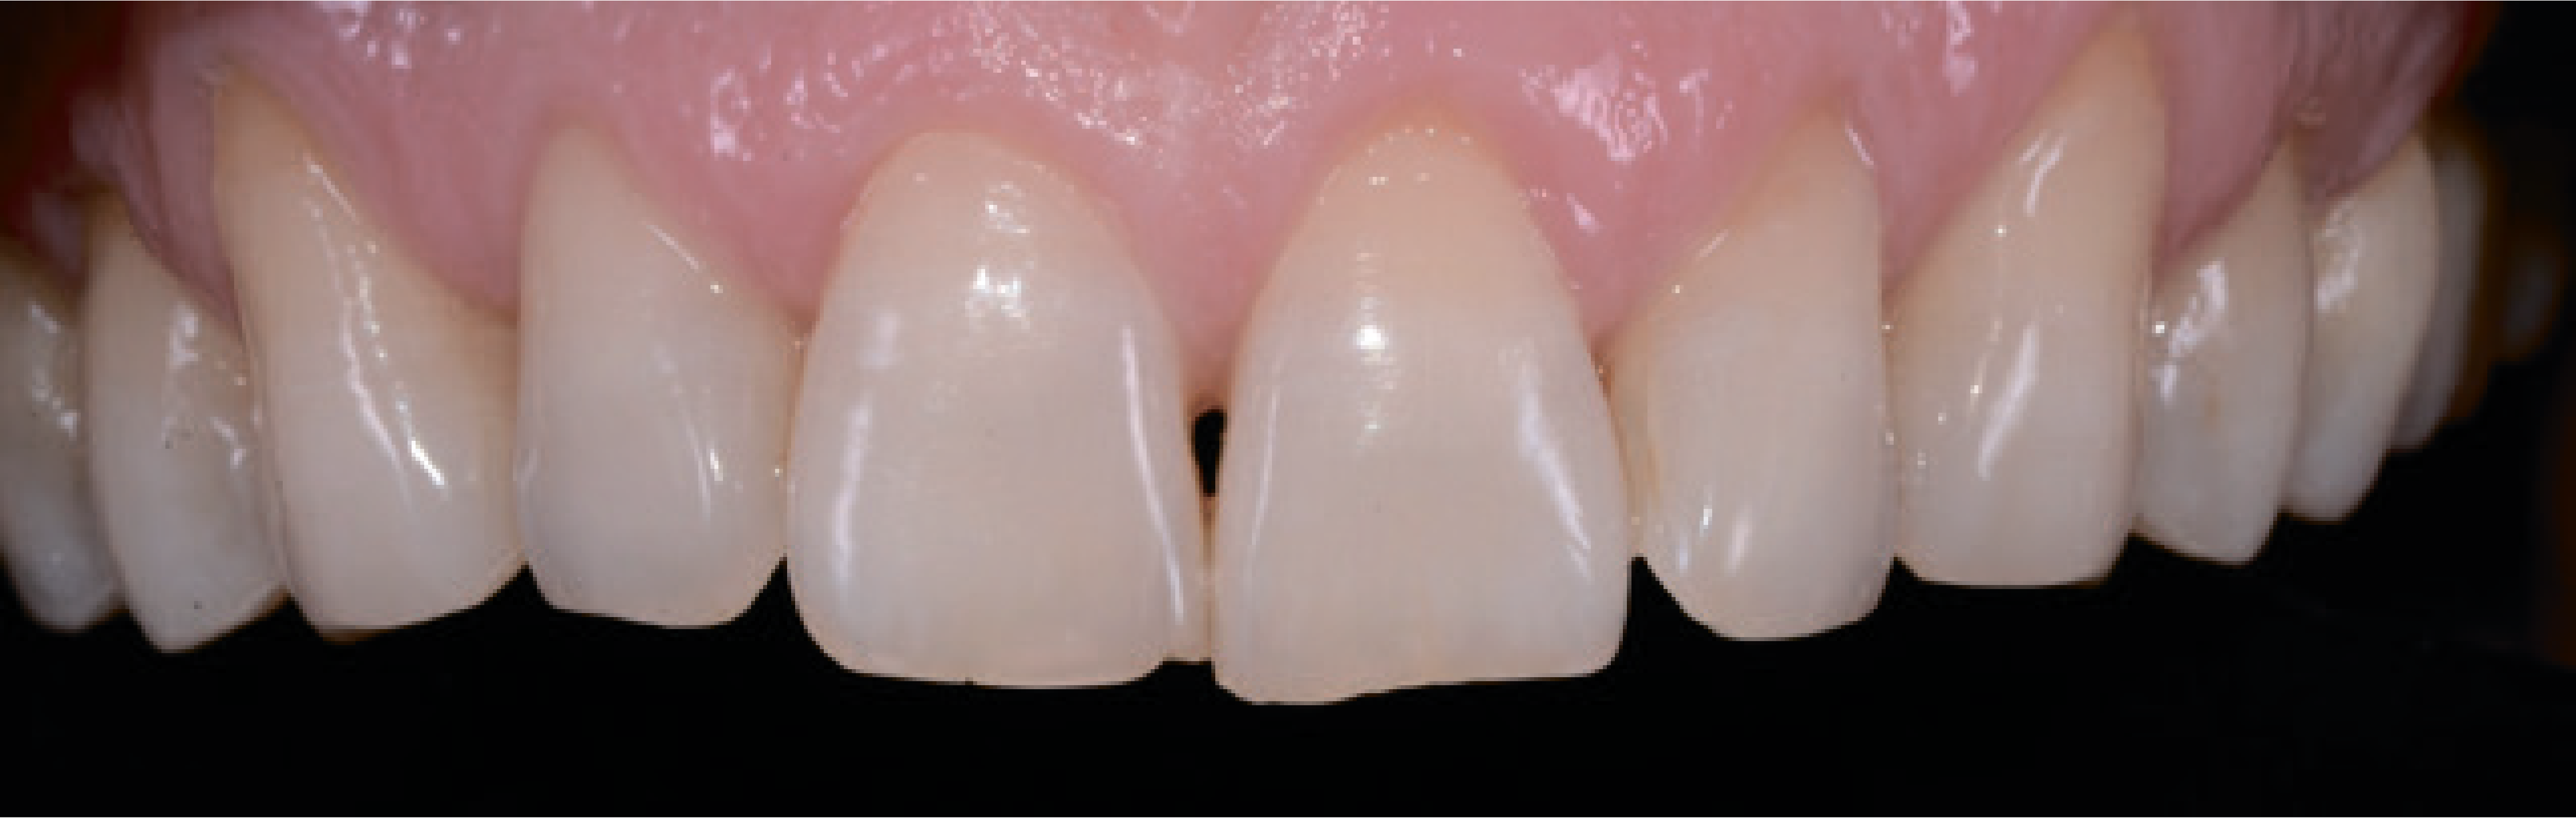

Загалом, він скаржився на жовтуватий колір і дистоповане положення зубів верхньої та нижньої щелеп. На перших фотографіях помітні певні естетичні дефекти. Різальні краї верхніх центральних різців були на різних рівнях (мал. 2).

Так, верхній лівий центральний різець був подовжений, і на ньому були явні ознаки стирання. Крім того, ікла були стерті, і це призвело до відсутності фізіологічних орієнтирів. Через положення верхньої губи під час посмішки було видно рівний ясенний край і правильну середню лінію на верхній щелепі, тимчасом як зуби нижньої щелепи були розташовані дуже близько один до одного (мал. 3).